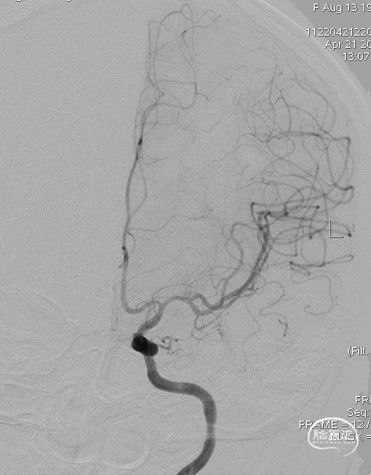

造影:右侧颈内动脉末端变细,大脑前及大脑中自起始部闭塞,脑底少量烟雾血管形成,汇聚使R-MCA少量分支显影。

右侧颈内动脉正位:

右侧颈内动脉侧位: